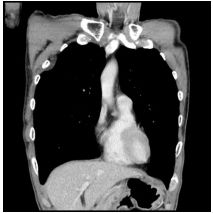

3. This 72-year-old diabetic man was taken to ER for productive cough for 10 days, and rapid progressive dyspnea for 2 days. He also had fever and chill for a week.